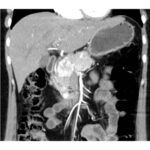

Paciente femenina de 48 años de edad que ingresa a Hospital Sanatorio Franchin por síntomas de cefalea y mareos, cuadro que se hace progresivo, presentando síncopes y posteriormente alteración del estado de conciencia. Los exámenes clínicos revelan una glucosa de 40 mg/dl, concomitante con insulina alta y péptido C elevado. Ingresa de forma programada para realización de duodeno pancreatectomía el 29 de mayo de 2021. Imágenes diagnósticas muestran estudio trifásico de tomografía de abdomen, lesión nodular en la cabeza del páncreas con ávido realce en fase arterial que en resonancia magnética se observa hiperintensa en T2, presenta restricción con la difusión y caída de la señal en el ADC. Además presenta realce tras la administración de contraste con gadolinio.

Estudio histopatológico reveló tumor neuroendocrino bien diferenciado grado 1.

Ahora bien, como se mencionaba al principio, el estudio ecográfico es de muy baja sensibilidad y se identifique o no la lesión por este estudio, nuestro siguiente paso en el algoritmo diagnóstico de esta lesión es la tomografía. Esta es la prueba no invasiva inicial, con una sensibilidad del 63% al 83%, y detecta del 70% al 80% de los tumores. Esta debe realizarse como un estudio trifásico: fase arterial temprana a los 30 segundos, fase venosa a los 70 segundos, fase tardía de 3 a 5 minutos. La característica de estos tumores por tomografía es que se presentan como una masa sólida que tiene un ávido realce en la fase arterial, cuyo realce se mantiene y se observa más tenue en la fase venosa y en los tiempos tardíos la lesión se homogeniza.

Para mi caso, y dando una visión general de los métodos de imagen no invasivos en esta revisión retrospectiva, solo a uno de los pacientes se le detectó la lesión por ecografía, donde se visualizó una lesión nodular hipoecogénica en el cuerpo del páncreas. A los demás pacientes se les detectó la lesión por tomografía en estudio trifásico, donde resaltan las características ya descritas por la literatura de lesiones hipervasculares con intenso realce en fase arterial, localizadas en diferentes partes del páncreas, como cabeza, cuerpo y cola.